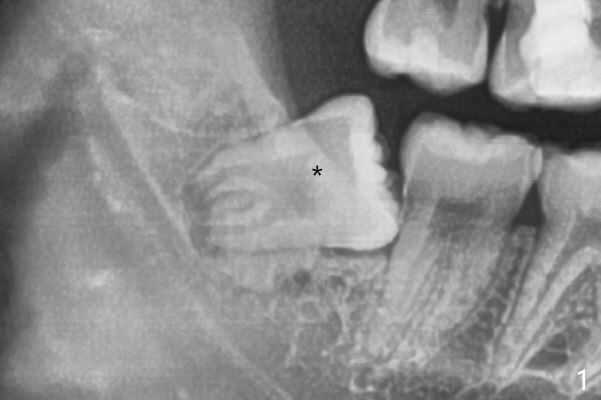

20岁女由于右下智齿疼痛就诊,诊断后,要求先拔除两个下颌智齿。外斜嵴好像跨越牙槽窝远中(图一:*),拔除似乎没有缩短外斜嵴长度(图二:*),牙槽窝放置胶原塞。